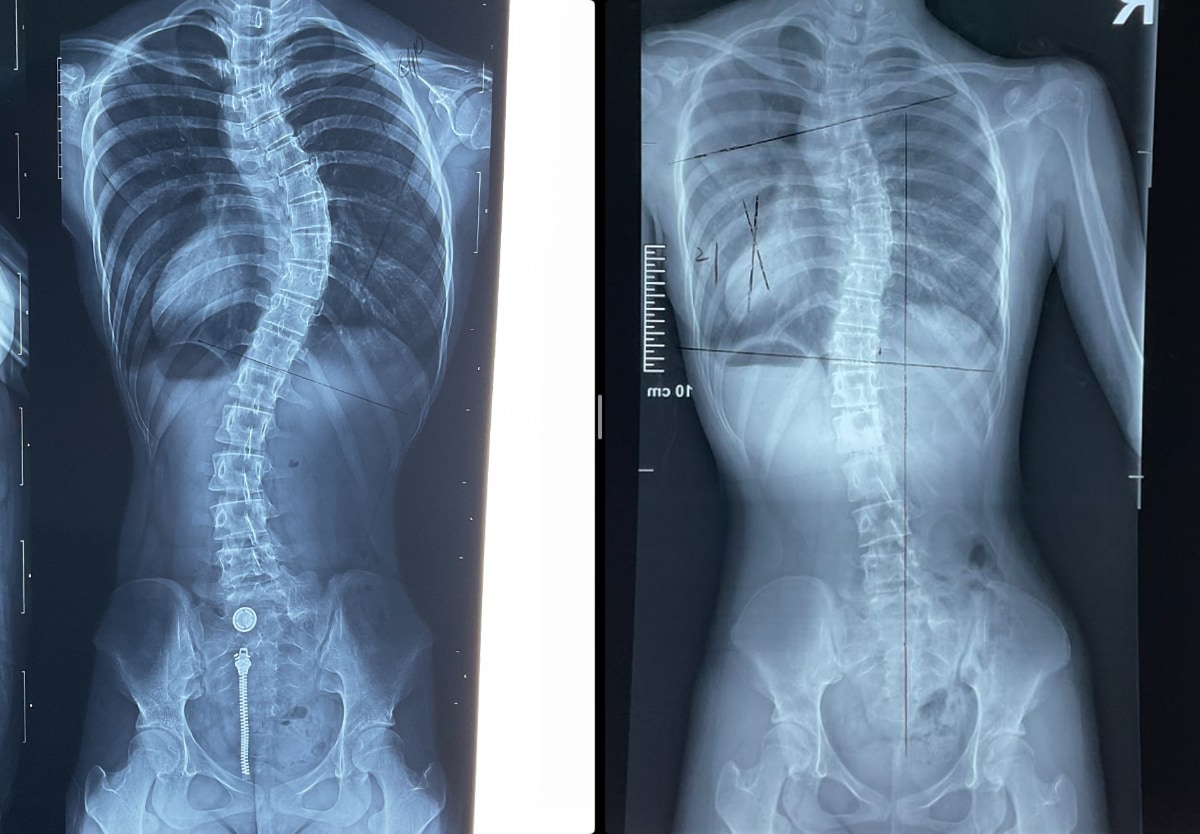

• Mild Scoliosis Case

Continue reading

• Scoliosis Case 41 to 21 degrees